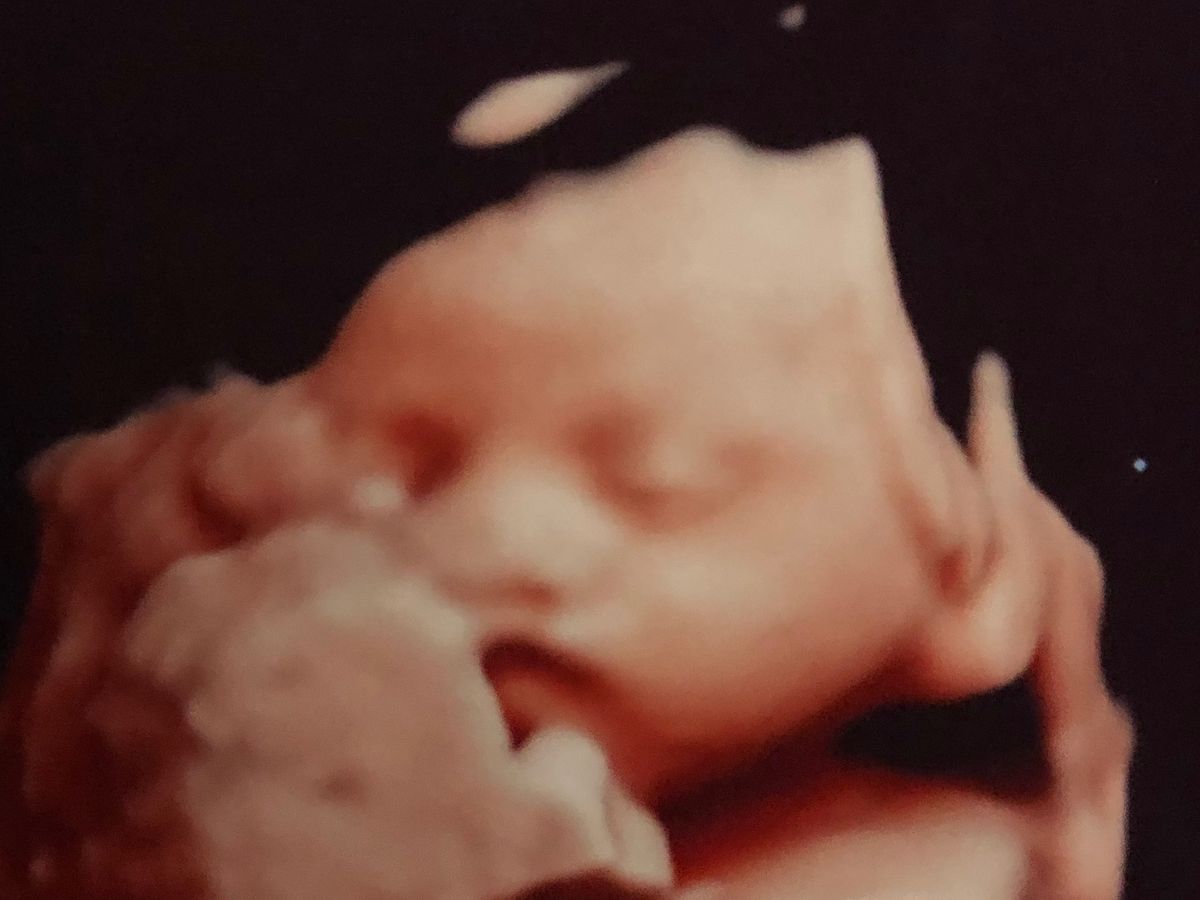

Baby Charlotte

Thank you for spending the time to read this . When we had our 20 week scan we found out our little princess would be born with a bilateral cleft lip and palate . It was very difficult news to hear knowing our daughter would have surgeries. As we met with all her amazing Craniofacial team we realized that she will require a lot of treatment/ special devices and weekly doctors visits with all her specialities. Thankfully insurance will cover most but not all. We know we have amazing family and friends that have been asking how they can help , any little donation will help reduce financial and emotional stress that is coming our way. I am beyond thankful for any support given .